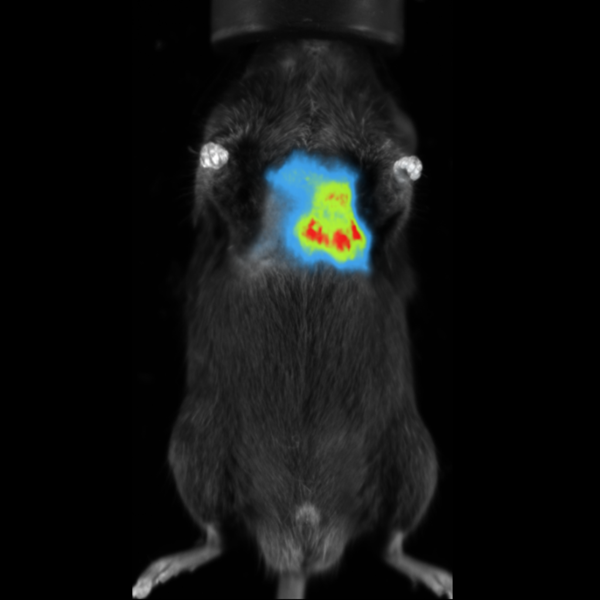

Fluorescence imaging

Vilber's dynamic range of emission filters can be employed in fluorescence imaging to identify fluorescent reporter genes or dyes in vivo.

Subcutaneous tumor expressing mCherry. Image Credit: Scintica Instrumentation Inc

mCherry Fluorescence Imaging in Subcutaneous Tumor in Mouse. Image Credit: Scintica Instrumentation Inc

In preclinical animal models, optical imaging can be used to non-invasively track the development and metastasis of cancer throughout the body.